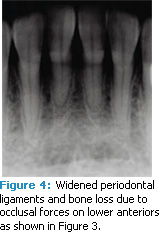

Occlusal trauma. An injury to the contact surfaces of opposing teeth, occlusal trauma leads to tissue changes within the attachment apparatus (tissues that support the teeth’s function) due to the pressure of occlusal forces. Any tooth that has premature, lateral, balance, or protrusive contact is more likely to experience occlusal trauma.1,2 Clinical symptoms include tooth pain, mobility, and widening of periodontal ligament spaces that can be viewed radiographically (Figure 1 to Figure 4). Excessive occlusal forces can injure the attachment apparatus and affect the temporomandibular joint, mastication muscles, pulp tissue, and integrity of tooth structure and restorations. Tooth wear. Patients may see or feel changes in tooth anatomy when a tooth is cracked or fractured (Figure 5 and Figure 6). Symptoms include sensitivity to pressure, cold, and/or sweets. The etiology of these cracks/fractures is multifactorial. Ratcliff et al suggest that excursive forces initiate cracks in teeth, which increase in the presence of parafunction.2 They found that stained or symptomatic cracks were age-related—demonstrating that the process is chronic. Staufer et al found a correlation between an increase in tooth fractures and lower anterior crowding (Figure 7). They concluded that an even occlusion, which eliminates interferences, may decrease the risk of cracks or fractures.3